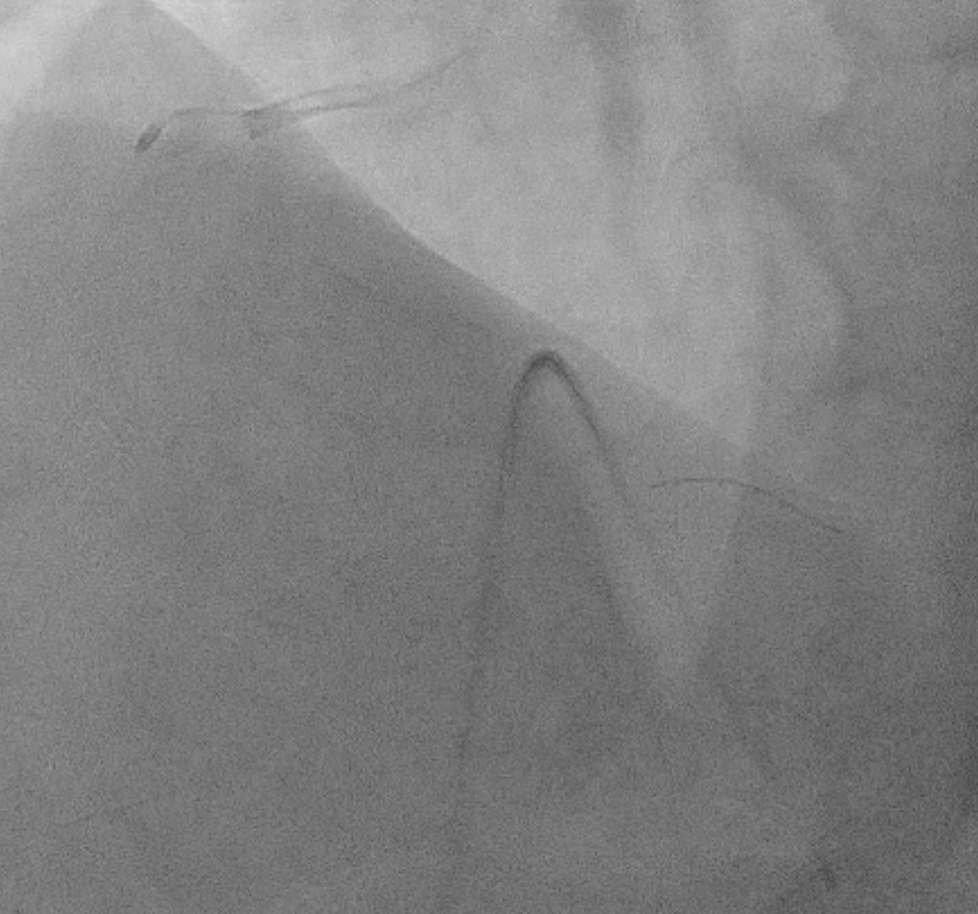

Dominant right coronary artery (RCA) with a heavily calcified, diffusely diseased segment extending from the ostium to the distal portion. The left anterior descending (LAD) and left circumflex (LCx) arteries show irregular but non-significant stenoses

PCI to RCA : Canulation using guiding catheter AL 0.75/7Fr, heparin was administered. Workhorse wire to distal PL. Initial attempt with a 1.5 ¡¿ 15 mm balloon failed to cross the distal lesion and subsequently ruptured. Rotational atherectomy was performed using a 1.5 mm burr at 160–180k rpm with three runs and one polishing pass. A 2.0 ¡¿ 15 mm semi-compliant balloon was then advanced from distal to proximal segments with the assistance of a guide extension catheter.IVUS evaluation demonstrated a 360¡Æ circumferential calcium arc and multiple calcium nodules extending from proximal to distal RCA. Lesion preparation was continued using sequential scoring balloon 2.0 mm and NC 2.5 mm, and cutting balloon 3.0 mm at high pressure. A ¡°dogbone¡± appearance was noted with the cutting balloon at the proximal RCA. An intravascular lithotripsy (IVL) balloon 3.0 mm was then applied to both distal and proximal RCA, delivering a total of 120 pulses (up to 8 atm).Repeat IVUS confirmed adequate calcium modification and optimal lesion preparation. Three overlapping drug-eluting stents (DES) were deployed: 3.0 ¡¿ 38 mm (distal–mid RCA), 3.5 ¡¿ 32 mm (mid RCA), and 4.0 ¡¿ 22 mm (ostial–proximal RCA), followed by sequential post-dilatation up to 4.0 mm. Final IVUS confirmed good stent apposition and expansion, with a minimal stent area of 6.36 mm©÷ at the distal RCA. TIMI 3 flow was achieved. Total contrast volume: 160 mL, Fluoroscopy time: 01:09:34 minutes, DAP: 232 Gy¡¤cm©÷